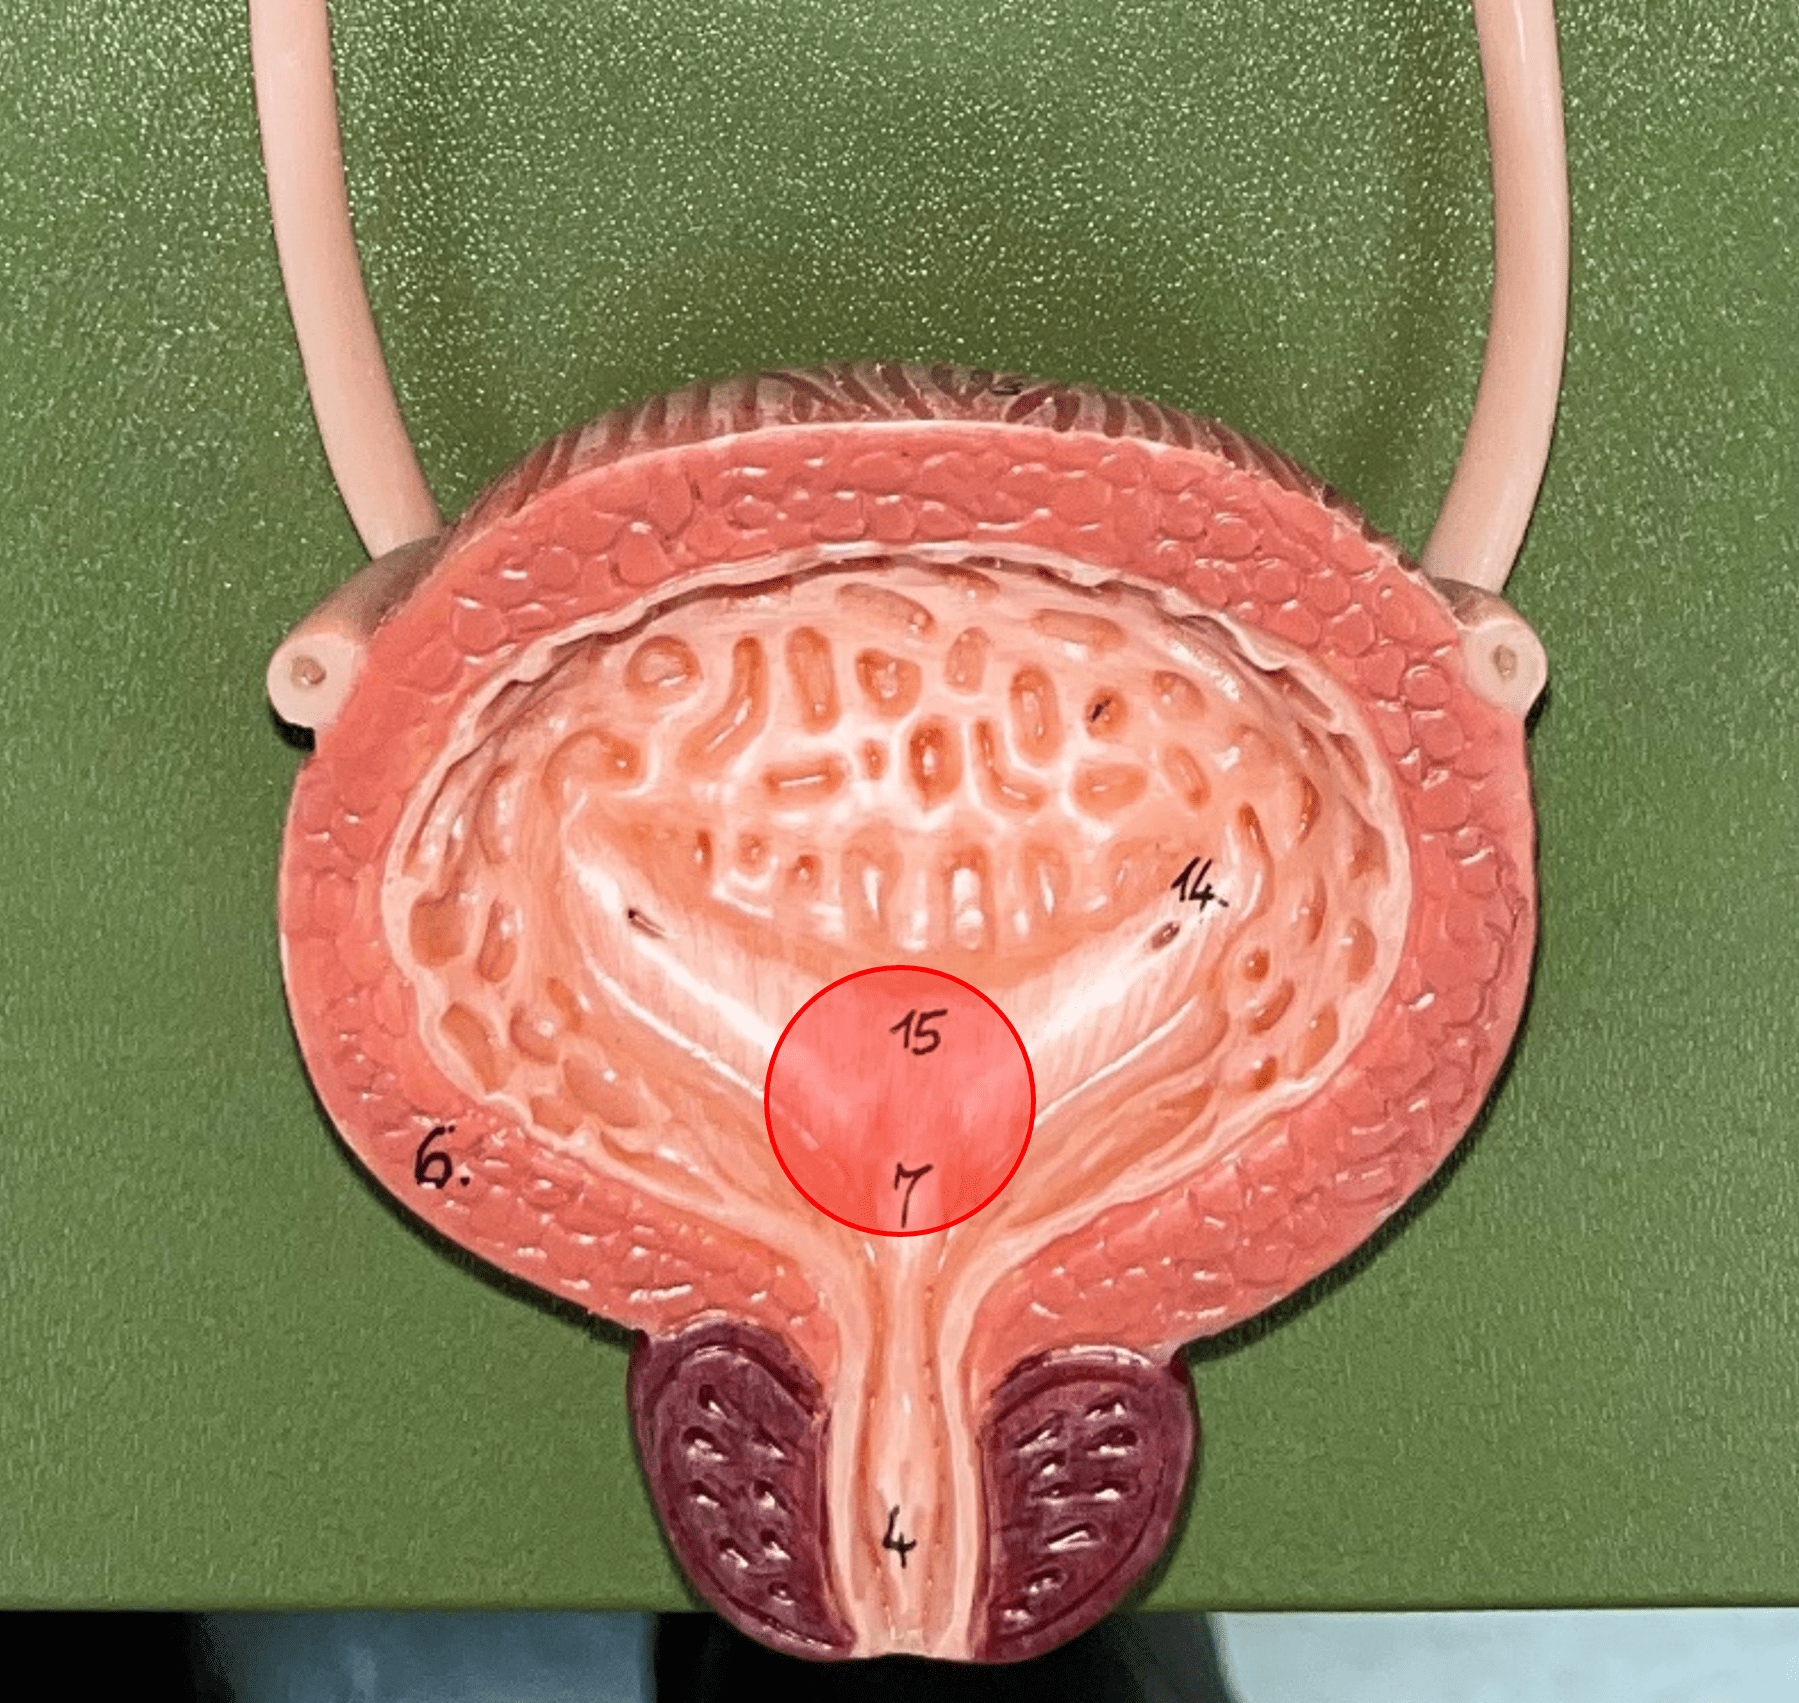

trigone

• Part of the urinary bladder.

• The triangle formed by the ureteral openings and internal urethra orifice.

• The triangle formed by the ureteral openings and internal urethra orifice.